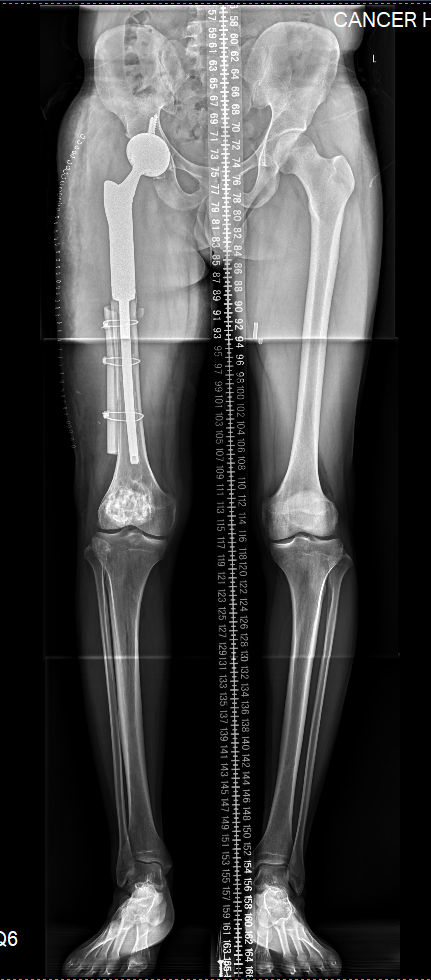

图片 5.png

术后双下肢全长片见假体位置良好,下肢长度等长,力线满意